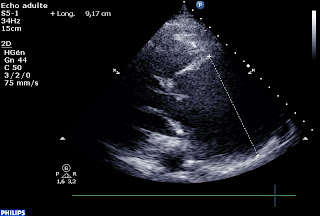

Par exemple, ce monsieur, qui n’a pas de chance, pas d’antécédent, pas de sécu et pas de famille : il a de la fièvre, un faux panaris, des hémocultures positives à staphylocoque, une insuffisance aortique significative récente et l’écho retrouve :

une dissection aortique! Enfin plutôt un anévrisme disséquant de l’aorte ascendante.

Anévrisme de 9cm…

IA moyenne avec PISA à 8 mm pour Vr à 0,3, soit une surface d’orifice régurgitant à 30 mm2

Sur cette coupe parasternale grand axe, la cusp anter-droite parait louche non?

Quel mécanisme(s) évoqueriez-vous pour expliquer cette fuite aortique?